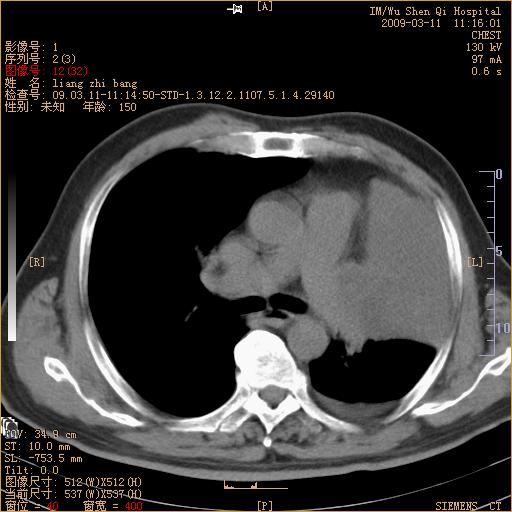

标题: CT18604:男,60岁,咳嗽一月余 [打印本页]

标题: CT18604:男,60岁,咳嗽一月余

1)考虑左肺上叶中央型肺癌并左肺上叶肺不张;建议必要时行纤支镜检查进一步明确诊断。2)左侧胸腔积液。

考虑左肺上叶中央型肺癌并左肺上叶肺不张

肺门肿块、支气管开口闭塞伴肺不张及胸水!典型的中心型肺癌变现!

1、左肺上叶中央型肺癌并上叶阻塞性肺不张。

2、左侧胸腔少量积液,右侧胸膜轻度增厚。

左肺们肿块并左肺上叶不张。考虑左肺中心性肺癌并左肺上叶不张及左侧胸腔积液